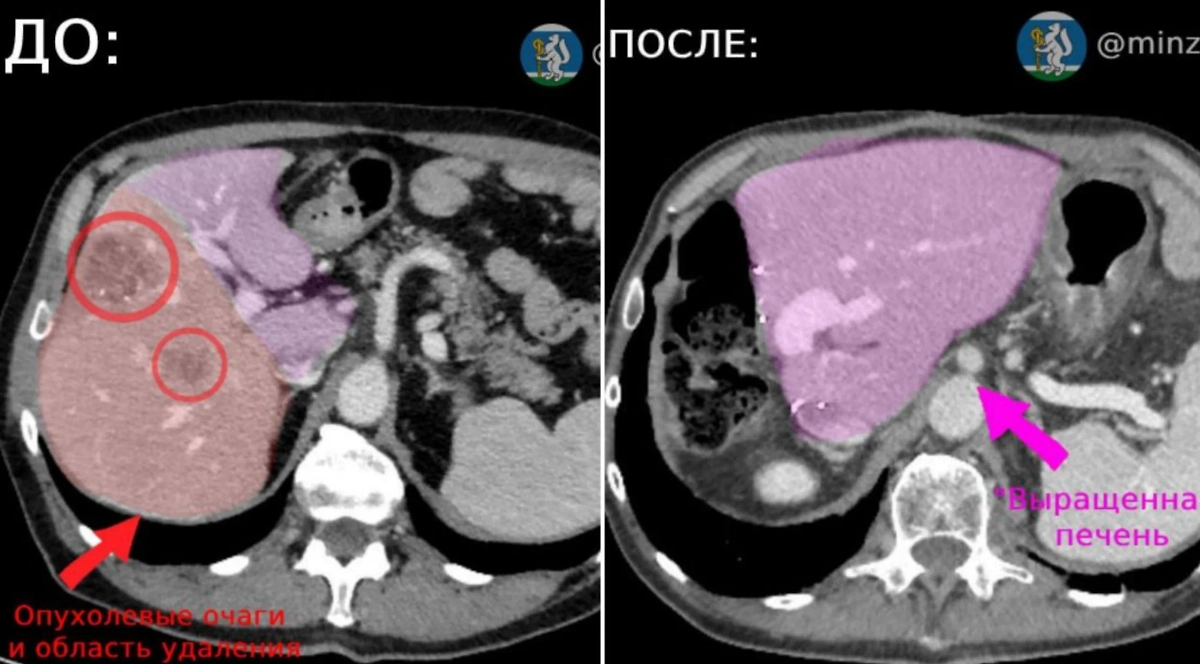

Свердловские онкологи провели уникальную операцию по восстановлению печени. Об успешном применении инновационной методики лечения пациента с опухолью печени сообщили в пресс-службе регионального областного онкодиспансера.

60-летнему пациенту удалили около половины поражённого органа, после чего стимулировали рост оставшихся здоровых тканей. Операция проводилась с применением современных технологий.

Печень пациента. Фото © VK / Минздрав Свердловской области

По словам медиков, подобные вмешательства требуют слаженной работы команды специалистов, включая абдоминальных и рентгенэндоваскулярных хирургов. Пациент сейчас чувствует себя хорошо и проходит плановые обследования каждые три месяца.